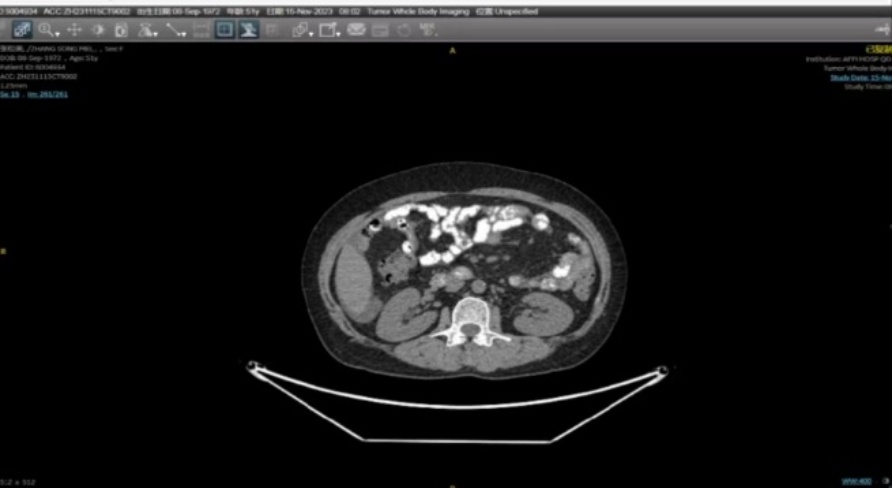

入院行妇科查体:子宫前位增大如孕3月大,质中,活动可,无压痛,右侧附件区扪及直径约15 cm肿物,有压痛,左侧附件区可扪及直径约6 cm肿物,有压痛,余未扪及明显异常。患者入院后完善相关辅助检查:实验室检查:血清肿瘤标记物:SCC:1.11 ng/mL,NSE:11.80 ng/mL,CA153:114.00 U/mL,CA 724:<1.50 U/mL胃泌素释放肽前体22.12 pg/mL;肝功:谷丙转氨酶35 U/L,谷草转氨酶37U/L;HPV:16型阳性;血常规、血凝常规、肾功、电解质检测等实验室检查未见明显异常。影像学检查:妇科超声:子宫肌层内见多个低回声结节,大者:前壁5.1 × 4.9 × 4.1 cm (外突),左侧壁6.4 × 6.3 × 5.6 cm (外突,推压内膜),右侧壁下段5.5 × 4.1 × 4.4 cm (明显推压内膜),盆腔偏右见14.7 × 11.8 × 8.1 cm、偏左见6.3 × 6.0 × 3.8 cm低回声团,形态欠规则,局部边界欠清,CDFI:内见点条状血流信号,腹盆腔内见液性暗区,腹腔较深处约2.8 cm,盆腔较深处约3.3 cm,透声可;PET-CT:1) 腹腔-盆腔内见2处不规则软组织密度肿块,内见低密度区,与双侧附件、部分肠管关系密切,不均匀代谢增高,SUVmax约4.8 (图1(a)图1(b));腹、盆腔积液;考虑肿瘤,附件或肠道来源可能性大,建议获得病理学诊断;2) ① 左肺下叶内前基底段磨玻璃密度结节,边界清,代谢略高于肺本底,SUVmax约1.0,不除外早期肺肿瘤,建议胸外科会诊;② 双肺数个小结节,未见异常代谢,建议CT随诊;③ 双肺慢性炎症;④ 右侧胸腔积液(少量);3) 左乳癌术后所见,局部未见复发征象;4) ① 左肾结石;② 子宫肌瘤;心脏超声:室间隔心肌肥厚(基底段),左室舒张功能减低;因HPV高危型阳性遂行宫颈活检病理:粘膜组织慢性炎,部分复鳞上皮呈低级别上皮内病变(LSIL/挖空细胞);下肢血管超声未见明显异常。

患有乳腺癌的女性与一般人群相比,发生恶性卵巢病变的风险增加。因此,尽管患者仍然没有症状,但进行腹盆腔定期检查很重要。如果有怀疑盆腔肿物的影像图像,伴CA125升高,应进行手术评估[4]。该患者术前PET-CT提示:腹腔–盆腔内2处不规则软组织密度肿块,内见低密度区,与双侧附件、部分肠管关系密切,不均匀代谢增高,SUVmax约4.8;腹、盆腔积液;考虑肿瘤,附件或肠道来源可能性大。结合既往病史,考虑该肿瘤倾向于卵巢来源可能性大,遂行全麻下开腹探查术,术中证实该肿瘤为卵巢来源且术后病理为乳腺浸润性小叶癌转移。